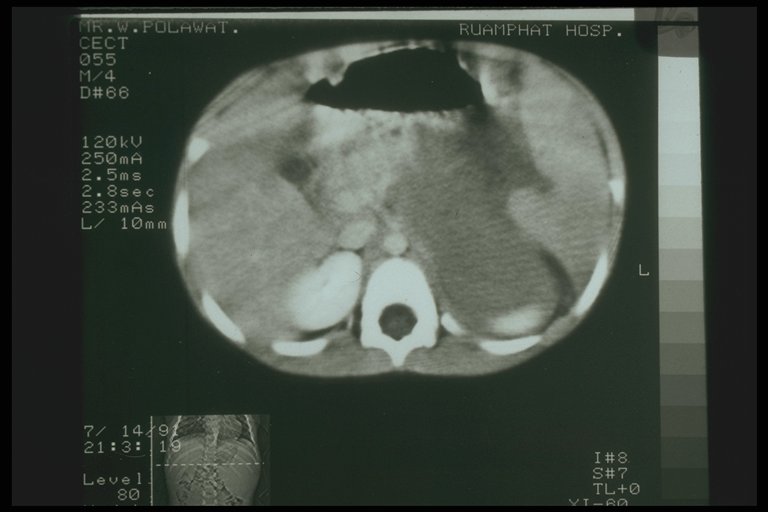

Pancreatic abscess. CT scan showed swelling of the body of pancreas with radiolucent area indicating abscess formation